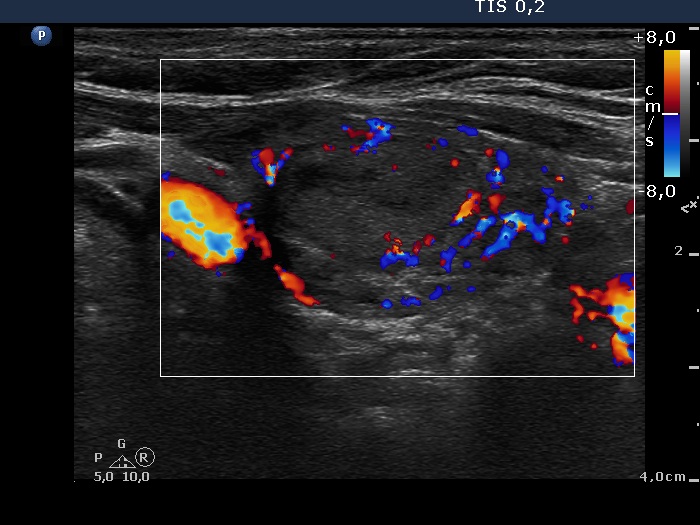

Ultrasonography. The thyroid was moderately hypoechogenic and inhomogeneous. There were multiple echonormal and minimally hypoechogenic discrete lesions in both lobes. Except for the one lesion in the left lobe, these did not correspond to nodule in a pathological sense, while in the event of a minimally hypoechogenic lesion in the left lobe, this possibility could not be excluded.

The patient had a deceptive ultrasound presentation on which the possibility of nodules in a pathological sense could not be excluded. It is worth analyzing the ultrasound images and video.